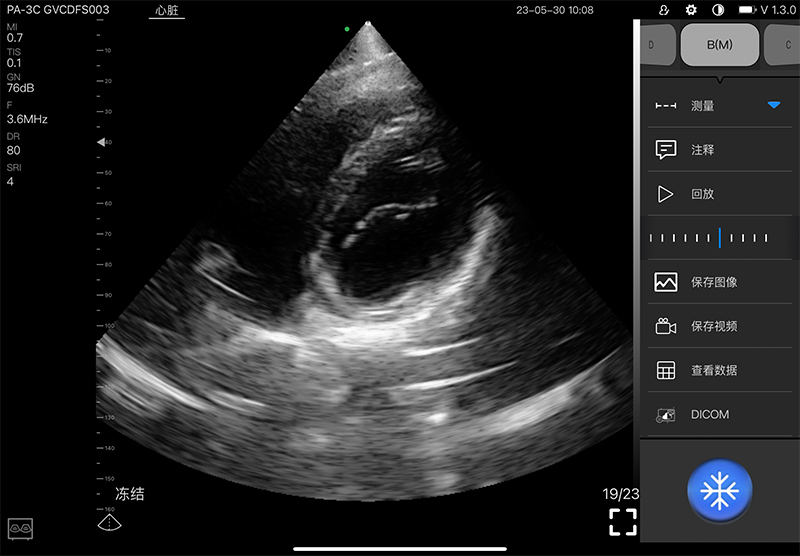

• 扫描方式: 电子相控阵扫描

• 阵元数:128

• 通道数:32

• 探头频率: 2.2-3.6MHz

• 增益30db-105db

• 扫描深度: 90/160/200/240mm,可调

• 扫描角度: 80°

• 显示模式: B、B/M、Color、PW、PDI

• 图像调节: 增益、焦点、反相脉冲谐波、降噪

• 图像帧频: 18f/s